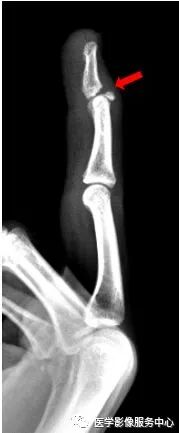

右手中指远节近端背侧关节处见游离骨片影,右手中指远节骨折。